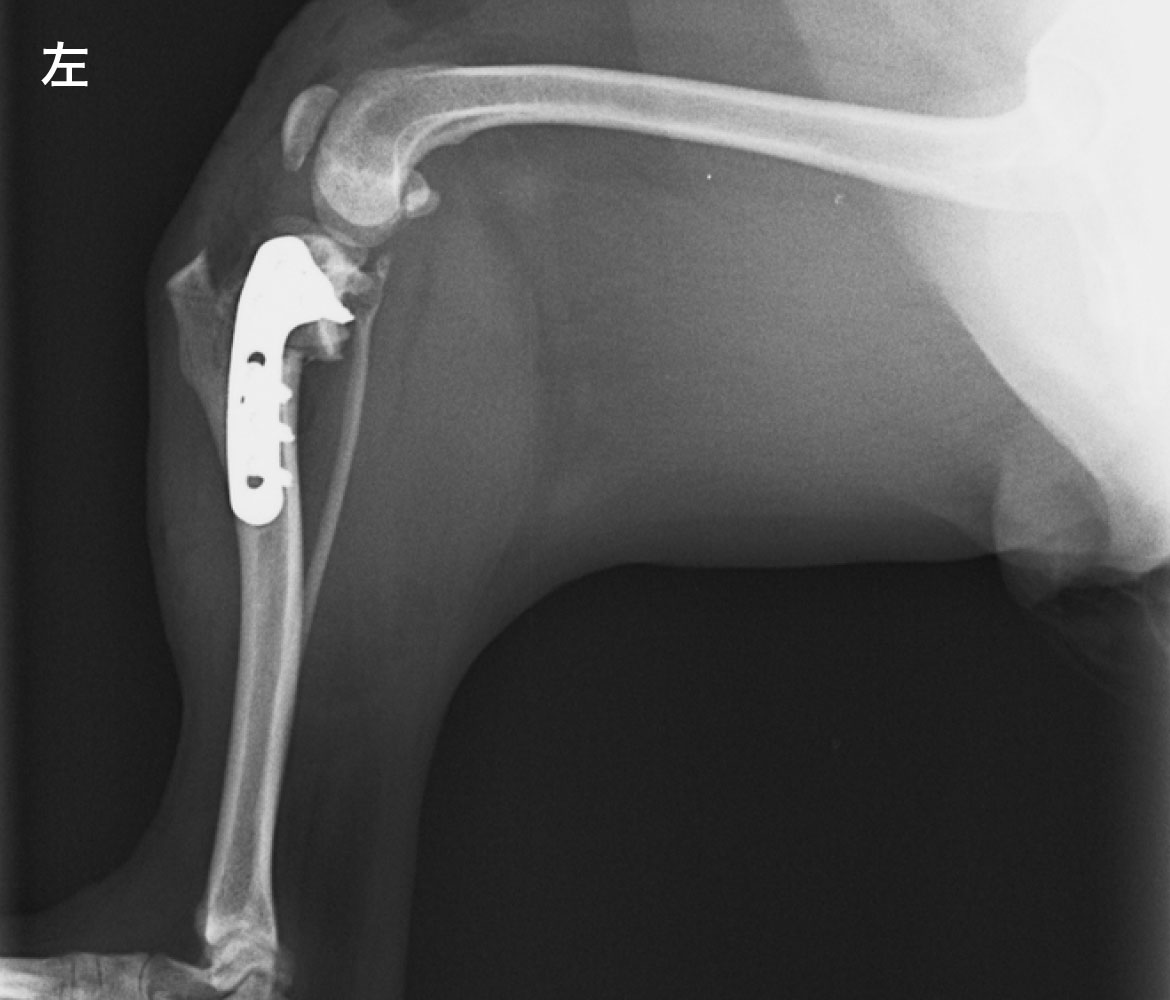

• After

TPLO 脛骨高平部水平化骨切り術

脛骨の傾斜が水平に近づくよう位置決めをして、弧を描くように骨切りを行います。切離後、骨片を回転させ、プレートとスクリューで固定します。